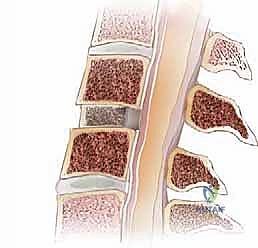

2. داء القرص التنكسي (Degenerative Disc Disease)

مع التقدم في العمر، تفقد الأقراص الفقرية محتواها المائي وتصبح أكثر تسطحاً وهشاشة. هذا التآكل يقلل المسافة بين الفقرات، مما يؤدي إلى احتكاك العظام ببعضها وتضييق مخارج الأعصاب.